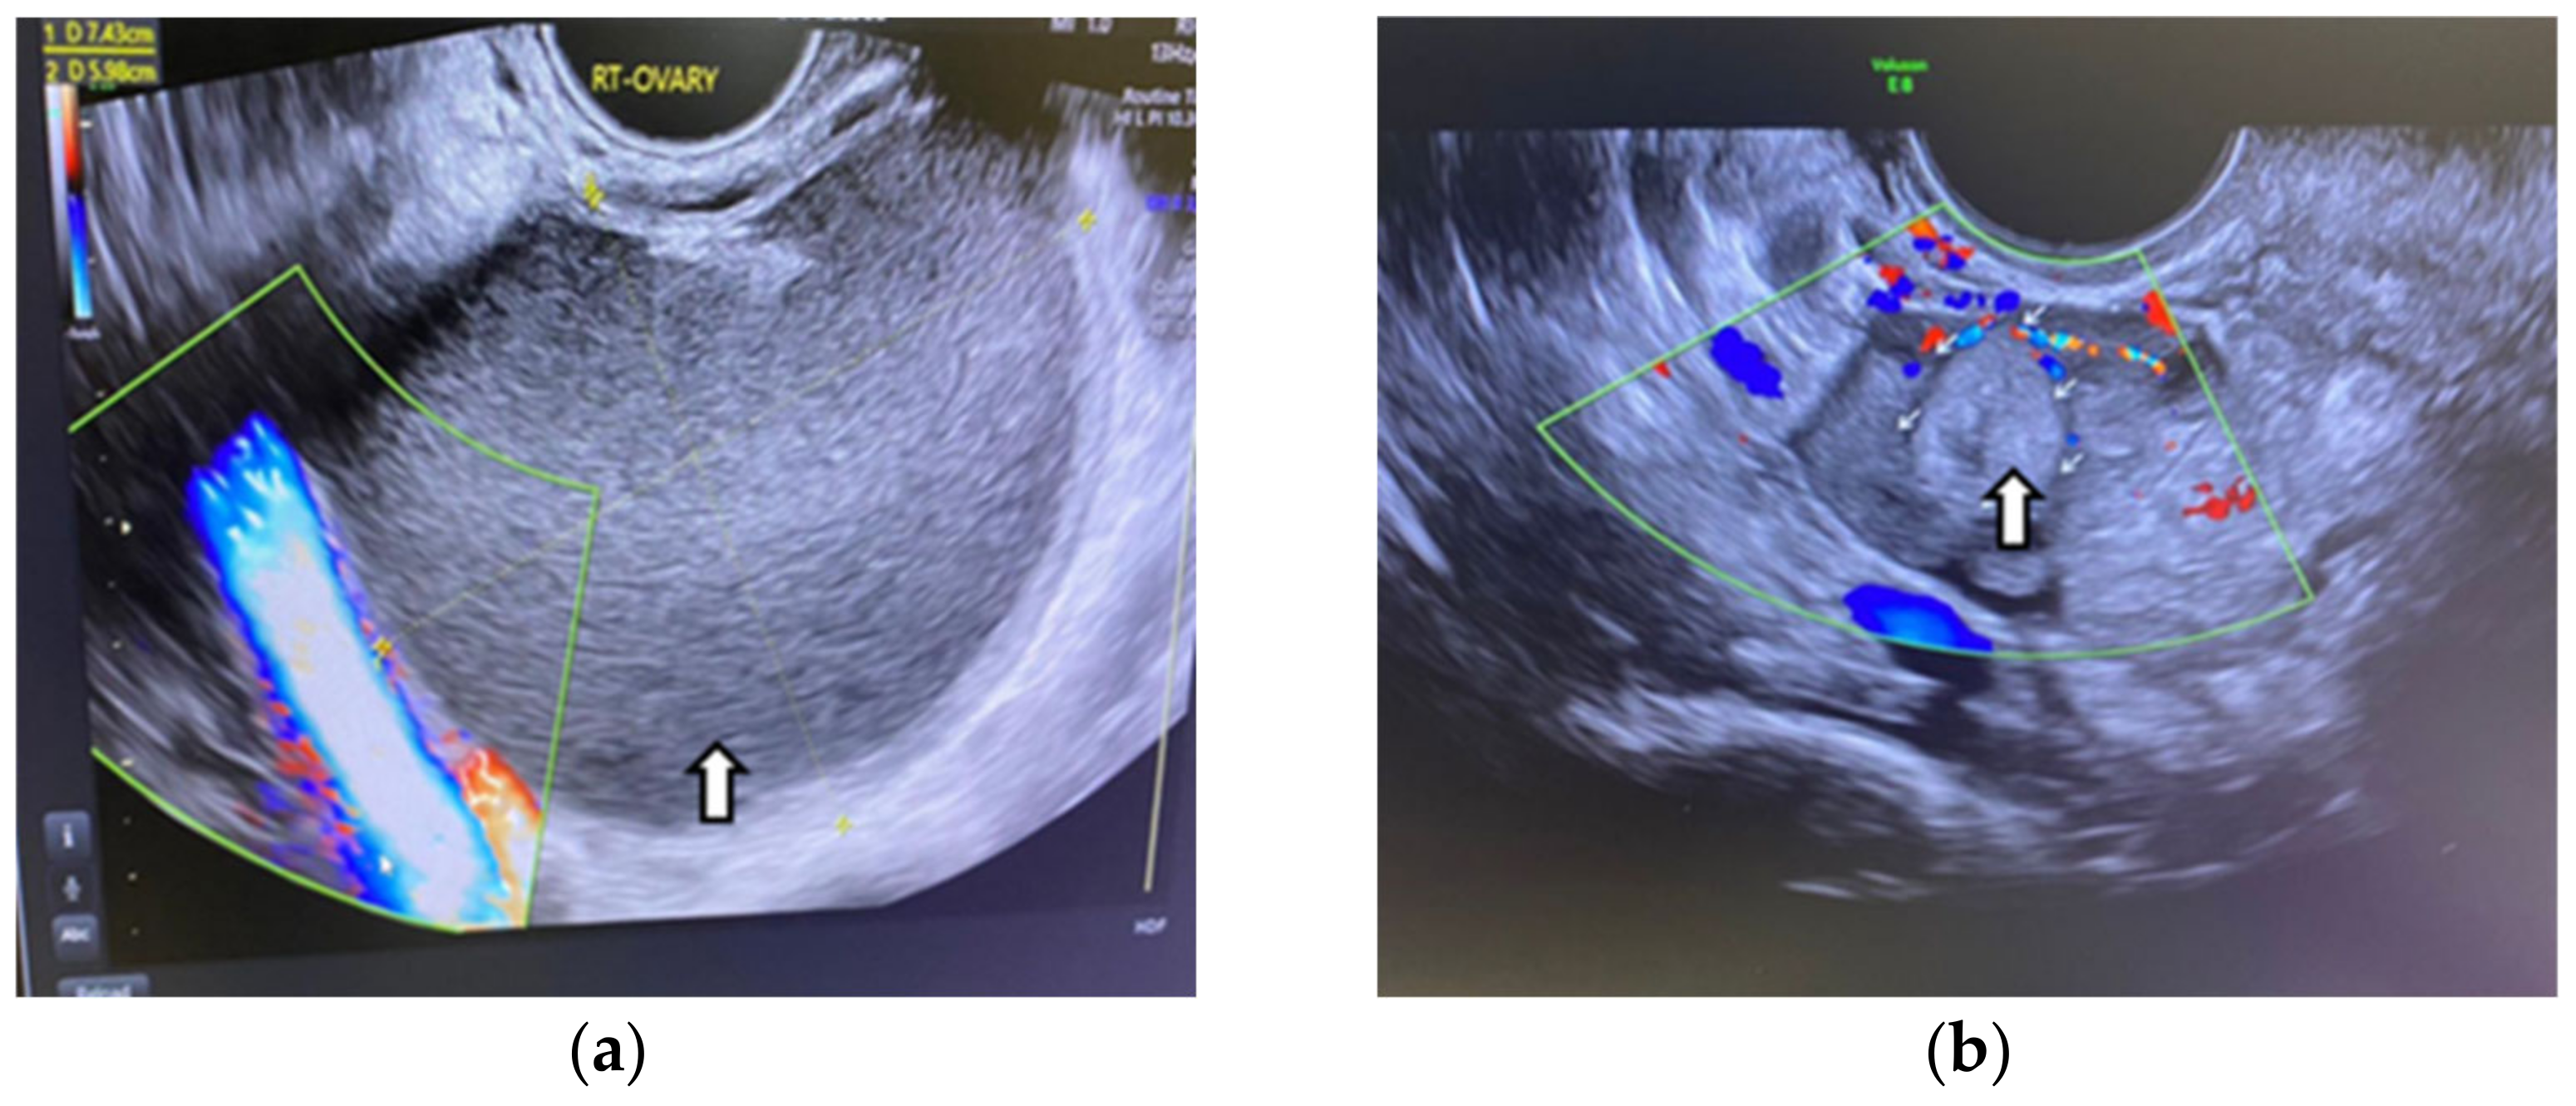

6.1.3. Imaging